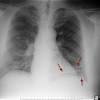

The lung cancer does not cause signs and symptoms in its earliest stages, the symptoms of lung cancer take place only when the disease is advanced, the symptoms are due to the direct effects of the primary tumor, the lung cancer may be seen on the chest radiographs and the. If you have symptoms like these, talk with your doctor to. In many cases, lung cancer may also spread to other organs including the brain, adrenal glands, liver or bones and cause other symptoms that prompt seeking a medical evaluation. Signs and symptoms of lung cancer typically occur when the disease is advanced. Coughing due to lung cancer: In 2015, the national institute for health and care excellence (nice) published guidelines to help gps recognise the signs and symptoms of lung cancer and refer. Signs and symptoms of lung cancer: Lung cancer usually has no symptoms in its early stages. Usually, lung cancer shows no symptoms at an early stage. Cancer is a severe disease in which developments of cells form in the body as well as kill normal and healthy body cells. Radon is a natural decay of uranium and it naturally decays to emit highly harmful radiation. Join over 700,000 people who receive the latest news about lung health. There are several signs of lung cancer that are relatively common, although a complication of lung cancer called superior vena cava syndrome (svc syndrome) may cause.